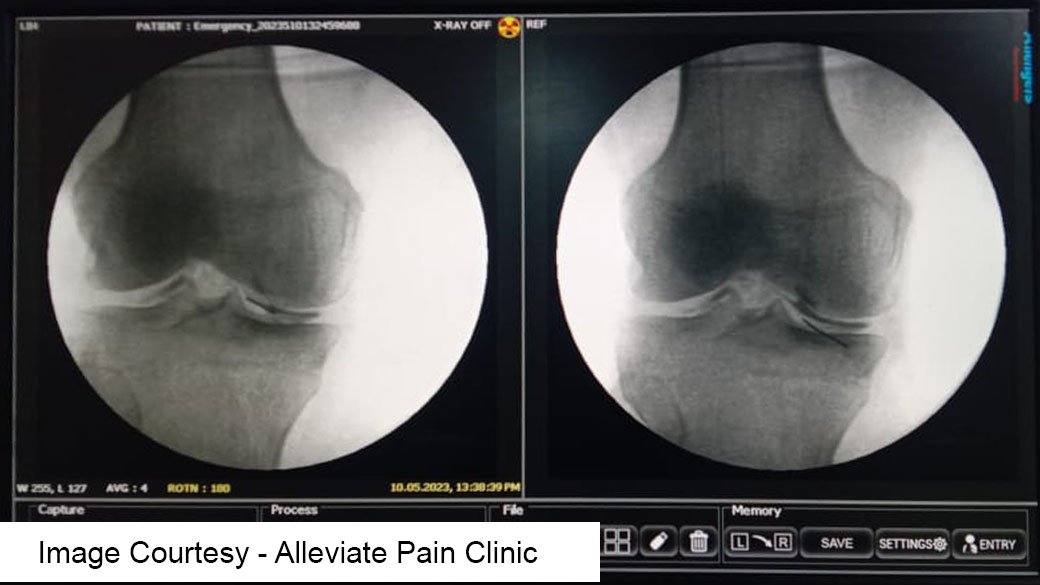

Fluoroscopy-Guided PRP Therapy

Fluoroscopy is a real-time imaging technique that uses continuous X-ray beams to visualize internal structures of the knee joint. It provides dynamic imaging, allowing our medical professionals to monitor the injection process in real-time.

Precise Needle Placement

Fluoroscopy guidance enables our practitioners to accurately position the needle within the target area of the knee joint, ensuring the precise delivery of PRP to the affected tissues. Platelet rich plasma

Visualization of Anatomical Structures

Fluoroscopy provides clear visualization of bony structures, soft tissues, and joint spaces, facilitating the identification of anatomical landmarks and potential areas of pathology within the knee joint.

Real-Time Monitoring

With fluoroscopy, our healthcare providers can monitor the dispersion of PRP within the joint space, ensuring uniform distribution and optimal coverage of the affected areas.